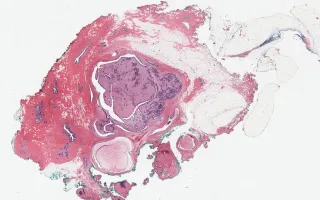

4.6 cm solid intraductal lesion in the retro-areolar area of left breast.

This fibroepithelial lesion shows an unusual intraductal growth pattern, and mimics a rare entity, intraductal fibroadenomatosis. Intraductal fibroadenomatosis is described as having features of flbroadenomas, papillomas and phyllodes tumours. In this case, the stromal expansion (with focal leaf-like pattern) and stromal cellularity were too pronounced, and the stromal mitotic activity too high (up to 7/10 high power fields), for a diagnosis of fibroadenoma.

Reported cases of intraductal fibroadenomatosis have not featured elevated mitotic activity or stromal atypia (Chung, A.et al., Breast J 2009, 14:193-195; Cummings MC, et al., Virchows Arch 2010, 456:105-106). Although the mitotic activity is more elevated than expected for a benign phyllodes tumour, no other worrisome features are observed - the borders are non-infiltrative, and there is no high-grade cytologic atypia, necrosis, heterologous differentiation or overgrowth in the stromal component. No atypia is identified in the ductal component.